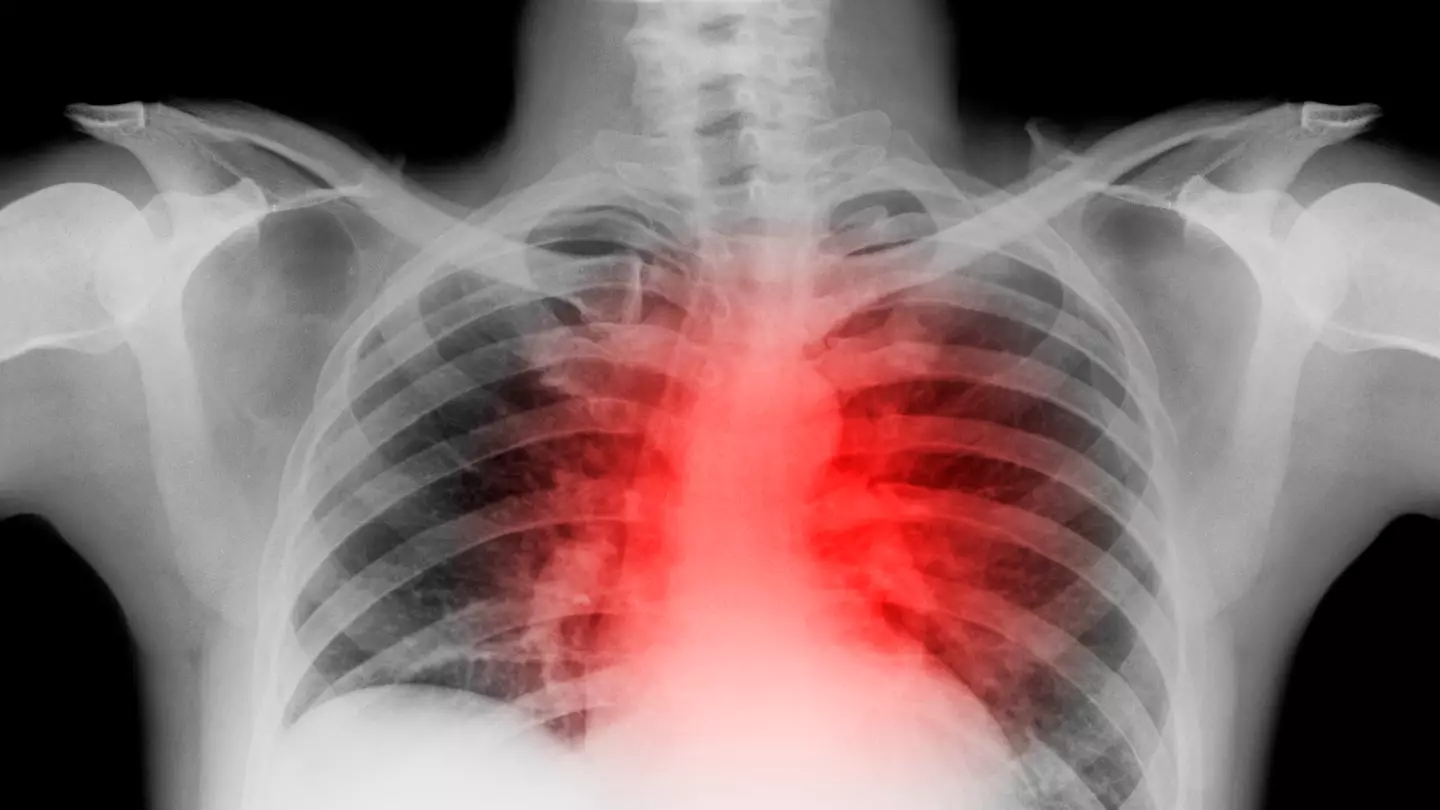

Dr Wilson underwent a cardiac catheterisation to find the source of the problem, which revealed he had endured a ruptured plaque that reduced blood flow to his heart muscle.